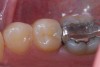

A patient presented for treatment with clinical and radiographic evidence of caries on the distal surface of the mandibular second premolar (Figure 1). The adjacent mandibular first molar had a defective amalgam restoration that was scheduled to be replaced with a core and prepared for a full crown at a future appointment. After administration of local anesthesia, a dental dam was placed. A sycamore wedge was firmly placed into the distal gingival interproximal embrasure before starting the preparation to achieve rapid separation of the tooth from its adjacent tooth to compensate for thickness of the thin, metal matrix (Figure 2). The tooth was prepared with a 245 bur with a high-speed handpiece and water spray. When restoring the proximal contact with composite resin, this author prefers to use a thin, dead-soft, stainless-steel matrix band that allows for shaping and achieving a positive, anatomic proximal contact. For this case the decision was made to use a silicone-covered split-tine ring with a sectional, thin, dead-soft, stainless-steel matrix. The silicone-coated ring is stable on the tooth and continues to apply pressure during restoration placement to ensure an anatomic proximal contact, while its shape allows for placement without interference from the gingival wedge. Also, the matrix has a tab extension that makes it easy to hold and place using a special forceps (Figure 3). Once the band was placed, an anatomic, flexible, polymeric wedge was placed using the same forceps.

Figure 3  Placement of a tab matrix with specialized placement forceps.

Figure 3